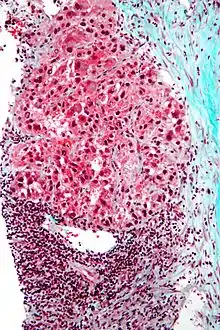

| Hepatocellular carcinoma in an individual who was hepatitis C positive. Autopsy specimen. | |

Microscopically, the four architectural and cytological types (patterns) of hepatocellular carcinoma are: fibrolamellar, pseudoglandular (adenoid), pleomorphic (giant cell), and clear cell. In well-differentiated forms, tumor cells resemble hepatocytes, form trabeculae, cords, and nests, and may contain bile pigment in the cytoplasm. In poorly differentiated forms, malignant epithelial cells are discohesive, pleomorphic, anaplastic, and giant. The tumor has a scant stroma and central necrosis because of the poor vascularization.[41] A fifth form – lymphoepithelioma like hepatocellular carcinoma – has also been described.[42][43]